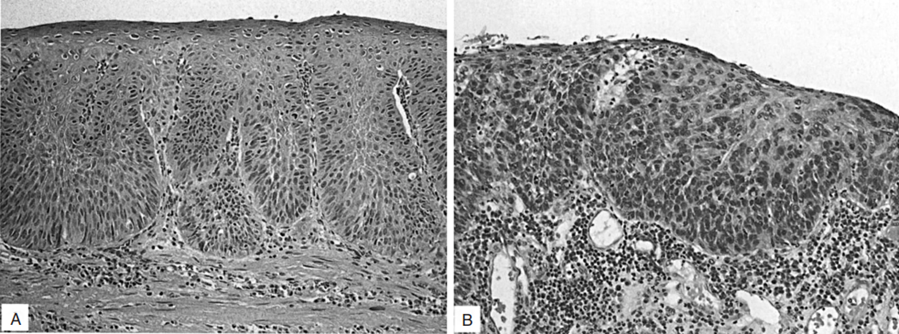

食管鳞状细胞不典型増生(上皮内瘤变)。(A)低度鳞状上皮不典型増生以新生鳞状上皮増生局限在上皮层的下一半为特征。(B)高度鳞状上皮不典型増生显示为上皮全层受累,新生鳞状细胞很大程度上有着结构混乱和细胞异型性。